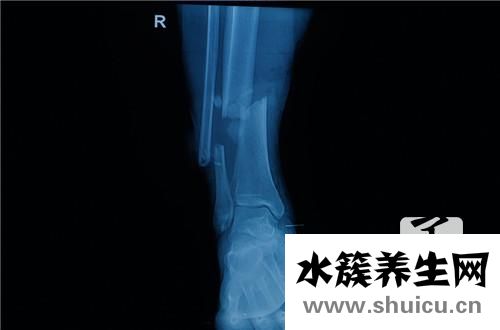

1、只要是惡性腫瘤,術后能活多長重點看是把握住了最佳手術治療機會。但大部分骨癌早期的找到較艱苦,就診時多為中晚期。假如是普查找到的癌腫,往往偏早,對手術后患者的生存率很有幫助。對于骨癌特別危險人群,最好能一年查體1~2次,對骨骼作通常X光片攝影,有助于早點查出骨癌。